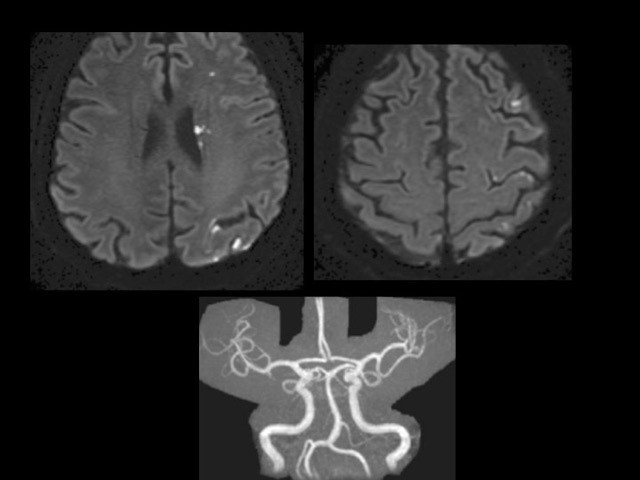

Une IRM cérébrale est réalisée.

Voici 2 images clés de l’IRM de diffusion et une l’angiographie par résonance magnétique (ARM) cérébrale

Question 6 : Que constatez-vous ?

Les deux coupes de l’imagerie de diffusion montrent des hypersignaux punctiformes multiples, tous localisés dans le territoire de l’artère cérébrale moyenne gauche. Il n’y a aucune anomalie visible sur l’ARM cérébrale (ni sténose ni occlusion artérielle, notamment dans le territoire ischémique atteint).

Question 7 : Vous retenez la présence d’hypersignaux punctiformes multiples sur la séquence de diffusion, également visibles sur la séquence FLAIR, dans le territoire de l’artère cérébrale moyenne gauche. Il n’y a pas de sténose ou d’occlusion des artères cérébrales ou cervicales. La séquence T2* est normale.